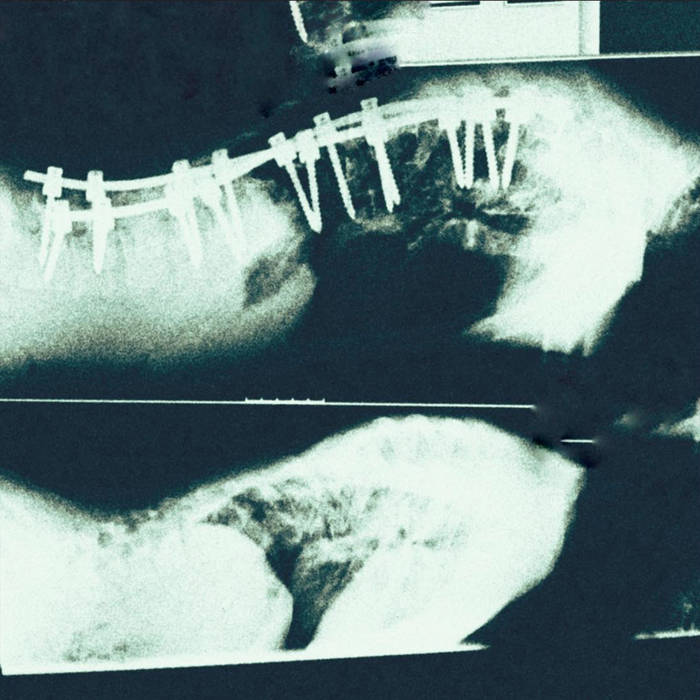

Belaver – Lain Prone